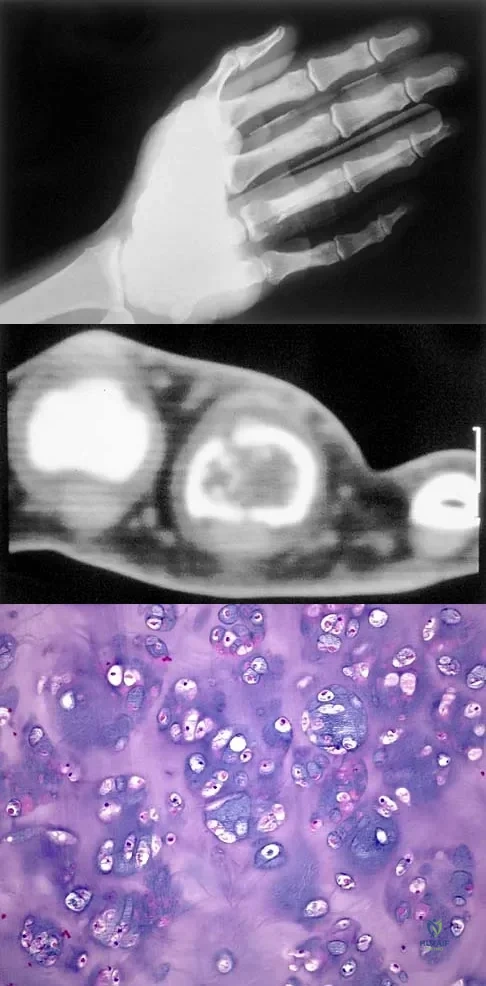

A 30-year-old woman has pain in her right hand. The radiograph, CT scan, and biopsy specimen are seen in Figures 38a through 38c. What is the most likely diagnosis?

Explanation